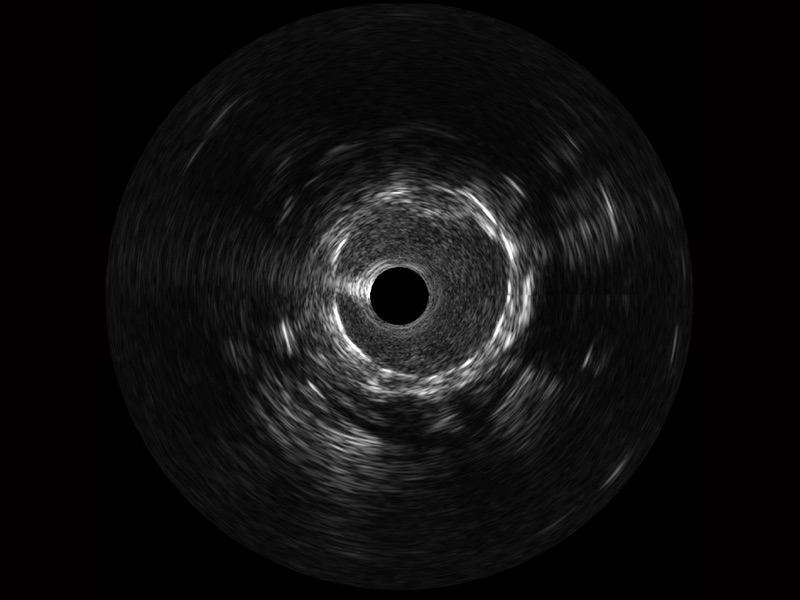

银河集团官网宽频IVUS图像

对比传统IVUS导管成像,银河集团官网宽频IVUS图像的近场支架梁显影更细腻,远场中膜外血管仍清晰可辨,兼顾远中近,兼顾分辨力与穿透深度